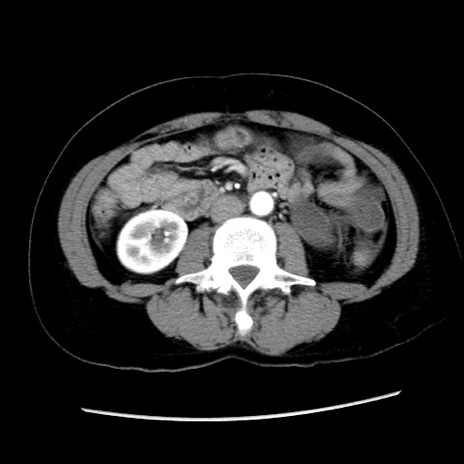

症例10(横断像)

【症例】 50歳代女性

【主訴】 腹痛

【現病歴】前日生レバーを食べた。今朝に排便あり。 昼前に突然発症の腹痛を生じ、当院救急外来を受診した。

【既往歴】 子宮筋腫にてで子宮全摘後

【身体所見】 意識清明、腹部:平坦、軟、下腹部やや左を中心に圧痛・反跳痛あり、筋性防御あり

【データ】WBC 7800、CRP 0.07